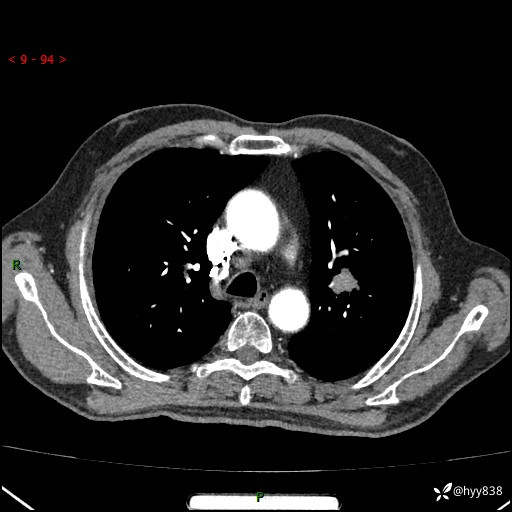

增强